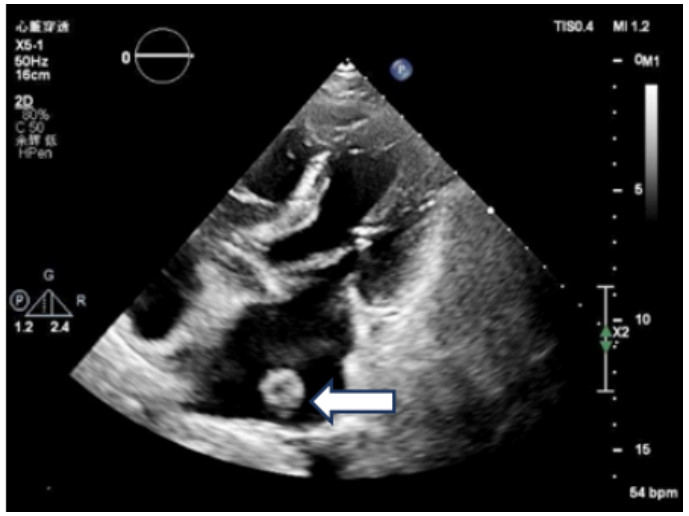

辅助检查:常规心电图示心房颤动。床旁经胸超声心动图示:原左房血栓影未显示(见图 3)。

| 注:左房内团块样回声影未见显示 图 3 患者本次入院当天常规经胸腔超声心动图 |